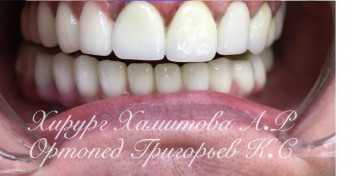

1 работа в портфолио

Имплантолог Хамитова Альбина Ренатовна владеет знаниями осуществления хирургического протокола имплантации зубов по стандарту «Штрауманн» (Швейцария), «Dentis» (Корея) и "Anthojur (Франция)». Освоенная специфика операций по стандартам указанных фирм-производителей, обширные знания методов диагностики и планирования предстоящего введения имплантантов в зависимости от начальных условий в полости рта, позволяют Альбине Ренатовне обеспечить возможность длительной стабильной фиксации конструкций даже в сложных клинических случаях. Характерными чертами имплантолога Хамитовой являются чуткость, рациональность и высокий профессионализм. За последние пять лет Альбина Ренатовна блестяще провела более 250 операций по имплантации зубов и костной пластике.